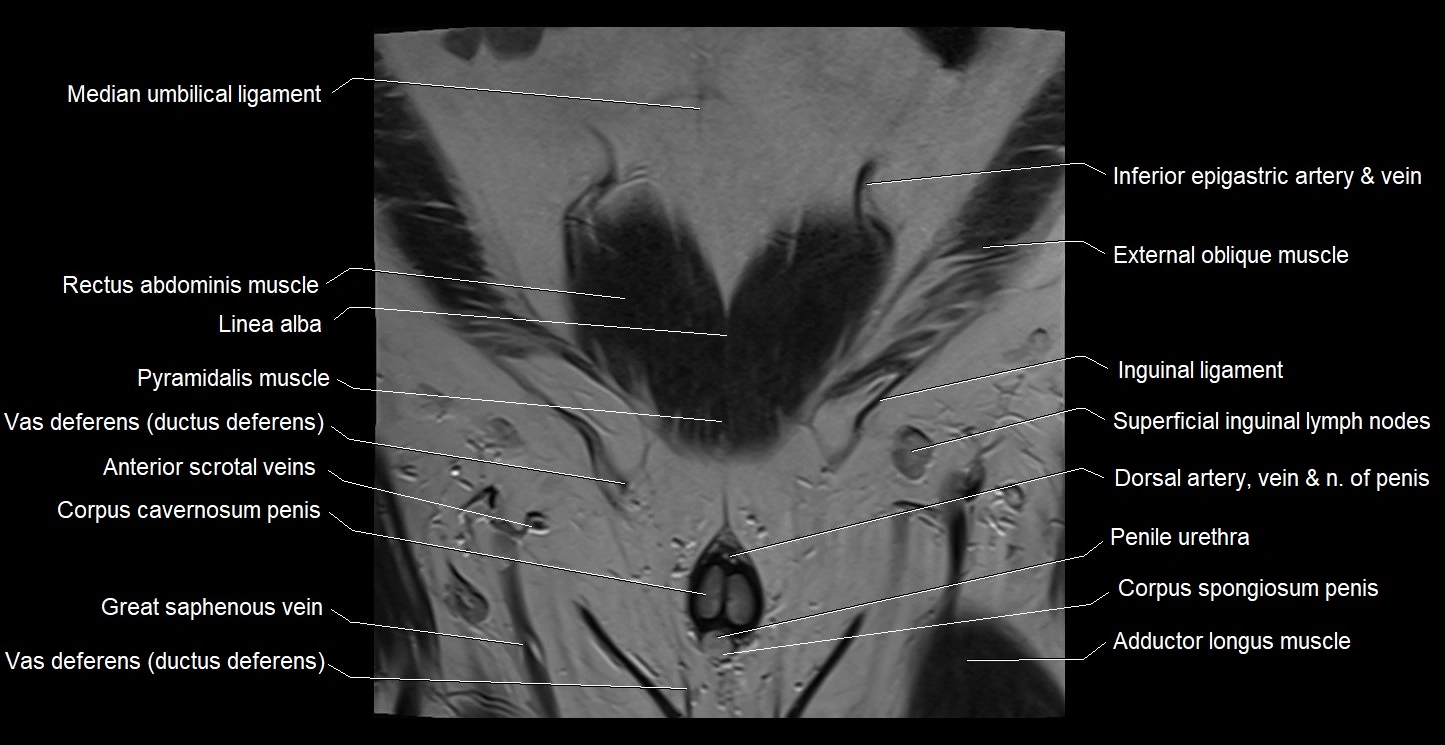

- Adductor longus muscle

- Linea alba

- Median umbilical ligament

- Penile urethra

- Superficial inguinal lymph nodes